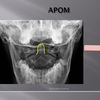

APOM ANATOMICAL LANDMARKS

maxillary sinus

29

frontal sinus

30

nasal aperature

31

nasal spine + septum

32

lower teeth

33

upper teeth

34

mandible

35

jugular process

36

A-P open mouth

rim of foramen magnum

37

anterior arch c1

38

posterior arch c1

39

A to P open mouth

lateral mass of c1

40

transverse process c1

41

medial inferior tip of occipital condyles

42

mastoid air cells

43

A-P open mouth view

pedicle shadow c2

44

spinous process c2

45

eop-iop

46

atlantal-axial joint space

47

vertebral bodies c2-c7

48

inferior articular surface c1

49

superior articular surface c1

50

A-P cervical

uncinate process of cervical vertebra

51

occipital-atlantal joint space

52

odontoid process